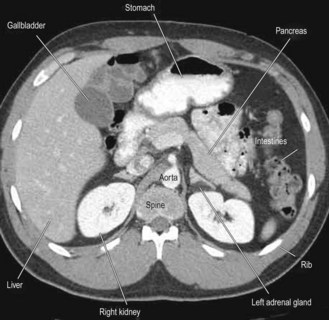

See Box 8.46 and Figures 8.29-33.

Fig. 8.29 Radiography in gastrointestinal disease.

(A) Air under the diaphragm on chest X-ray due to perforated duodenal ulcer. (B) Dilated small bowel due to acute intestinal obstruction. (C) Dilated large bowel due to toxic megacolon. (D) Dilated loop of large bowel due to sigmoid volvulus.